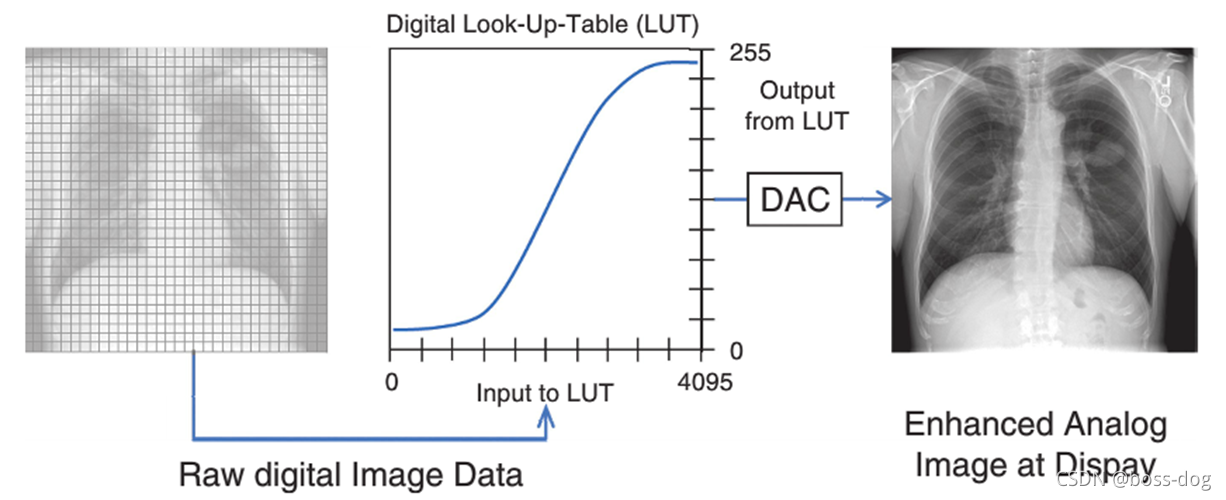

Display contrast(显示器地对比度)

医学图片中希望把最黑的、最亮的、中间的能够完美地显示出来。

上图中如何将灰度转换为显示器上的实际密度:

窗口宽度(Window width,W)

window level(L)

饱和至黑色:L - W/2

饱和至白色:L + W/2

1.检测器信号范围是0-4000计数/像素。

2.PC显示器相对亮度0-2000。

3.图像具有有用区域的信号范围为500-3000计数/像素。

像CT的话,窗口很宽,从负一千到正一千,如果全部显示出来的话,人眼不一定能够把那些细节检测出来看出来,所以针对CT,可以调整图像。